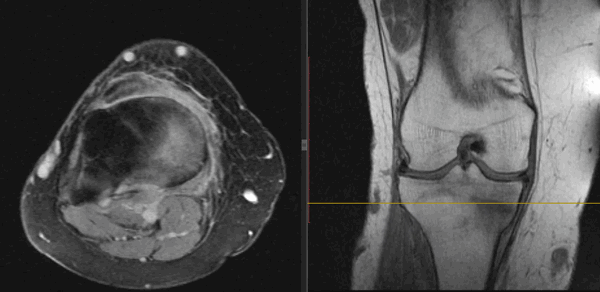

На Т2-ВИ в сагиттальной и корональной плоскостях определяется стресс-перелом дистальных отделов малоберцовой кости.

МРТ выявляет скрытые переломы. Это такие случаи, когда рентген не покажет линию перелома несмотря на то, что она есть. Если после травмы боли не проходят, а рентгеновский снимок не выявил никакой патологии, пациенту рекомендуют сделать МРТ соответствующей области.

С помощью МРТ более точно определяют свежие переломы: видны отек костной ткани, разрушение костных трабекул. МРТ хорошо дифференцирует свежие переломы от застаревших случаев.

Расшифровка и как выглядят переломы на снимке МРТ?

Плотное вещество кости лучше исследовать на снимках КТ. На МРТ снимках кость – самая темная ткань, на КТ – наиболее яркая и светлая. Зато МРТ лучше выявляет сопутствующие переломам повреждения костного мозга, спинного мозга, нервов, сухожилий, мышц, связок.

Свежие переломы всегда сопровождаются отеком мягких тканей вокруг костей, отеком самого вещества кости. На снимках это выглядит как затемнение без четких контуров.

На Т2-fs-ВИ в сагиттальной плоскости определяется разрыва пяточного сухожилия.